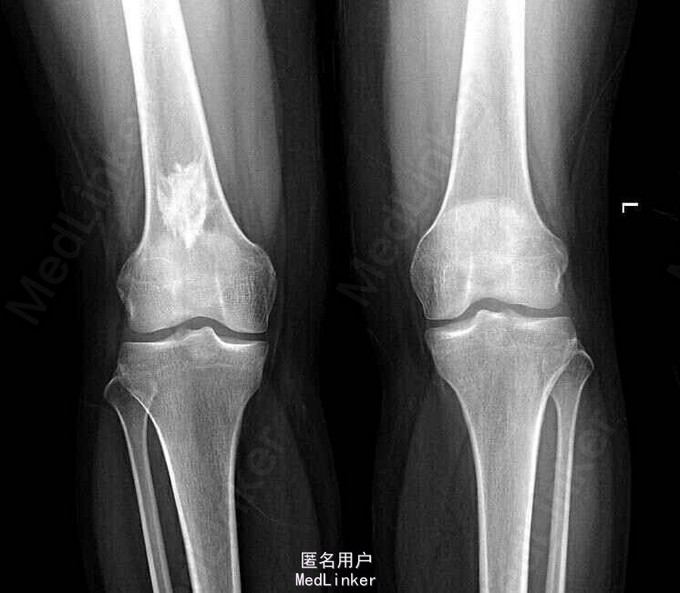

查体:右股骨下段轻压痛,未触及明显肿物,周围皮肤无红肿热痛。 膝关节正侧位(双侧) 右侧股骨下段骨髓腔内可见片状高密度灶,边缘不规则,余双侧膝关节组成骨形态可,骨皮质连续,骨小梁清晰,关节面光整,关节对位良好,关节间隙未见明显异常。周围软组织未见明确肿胀。